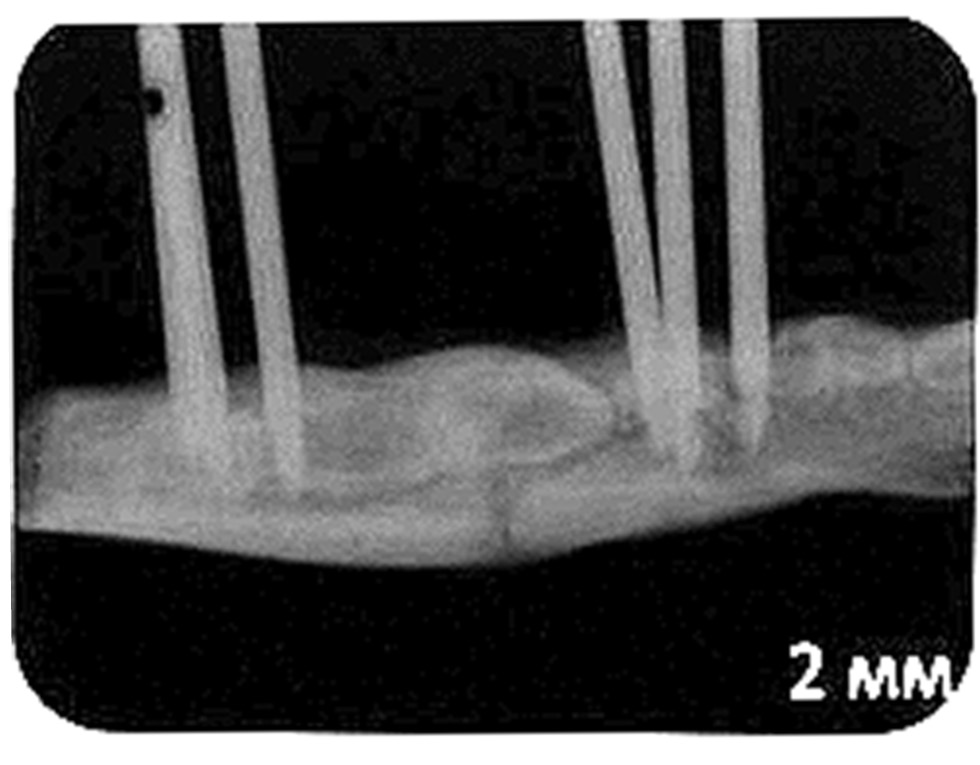

Были подобраны опытные животные (щенки) одного возраста и комплекции, которых разделили на группы. На базе ветеринарного центра в условиях общего внутривенного наркоза устанавливали дистракционные аппараты на тело нижней челюсти собак справа и слева (рис. 1) с одномоментным рентгенологическим контролем фиксации аппаратов и линии проведённой остеотомии. На шею каждой собаки фиксировали защитный пластиковый конус (воротник) для предотвращения повреждения аппаратов и комплекта электроники.

Рис. 1. Дистракционное устройство, зафиксированное на тело нижней челюсти собаки справа.

Fig. 1. The distraction device fixed on the lower jaw body of the dog on the right.

При анализе рентгенограмм, сделанных в период ретенции во всех группах, определялись характерные признаки оссификации новообразованных регенератов независимо от темпа дистракции между фрагментами; при этом наиболее зрелым и рентгенологически качественным представлялся регенерат с темпом непрерывной дистракции 2 мм в сутки (рис. 2).

Рис. 2. Рентгенограмма регенерата, полученного с темпом непрерывной дистракции 2 мм в сутки.

Fig. 2. X-ray of the regenerate obtained with a continuous distraction rate of 2 mm per day.

Режим дистракции был дробным — 1 мм в сутки по 0,25 мм за 4 приёма в течение 20 дней, общая величина дистракции составила 2,0 см (рис. 5).

Рис. 5. Рентгенограмма пациента В., 7 лет, на 20-е сутки дистракции, величина дистракции 2,0 см.

Fig. 5. X-ray of the patient V., 7 years old, on the 20th day of distraction, the amount of distraction is 2.0 cm.